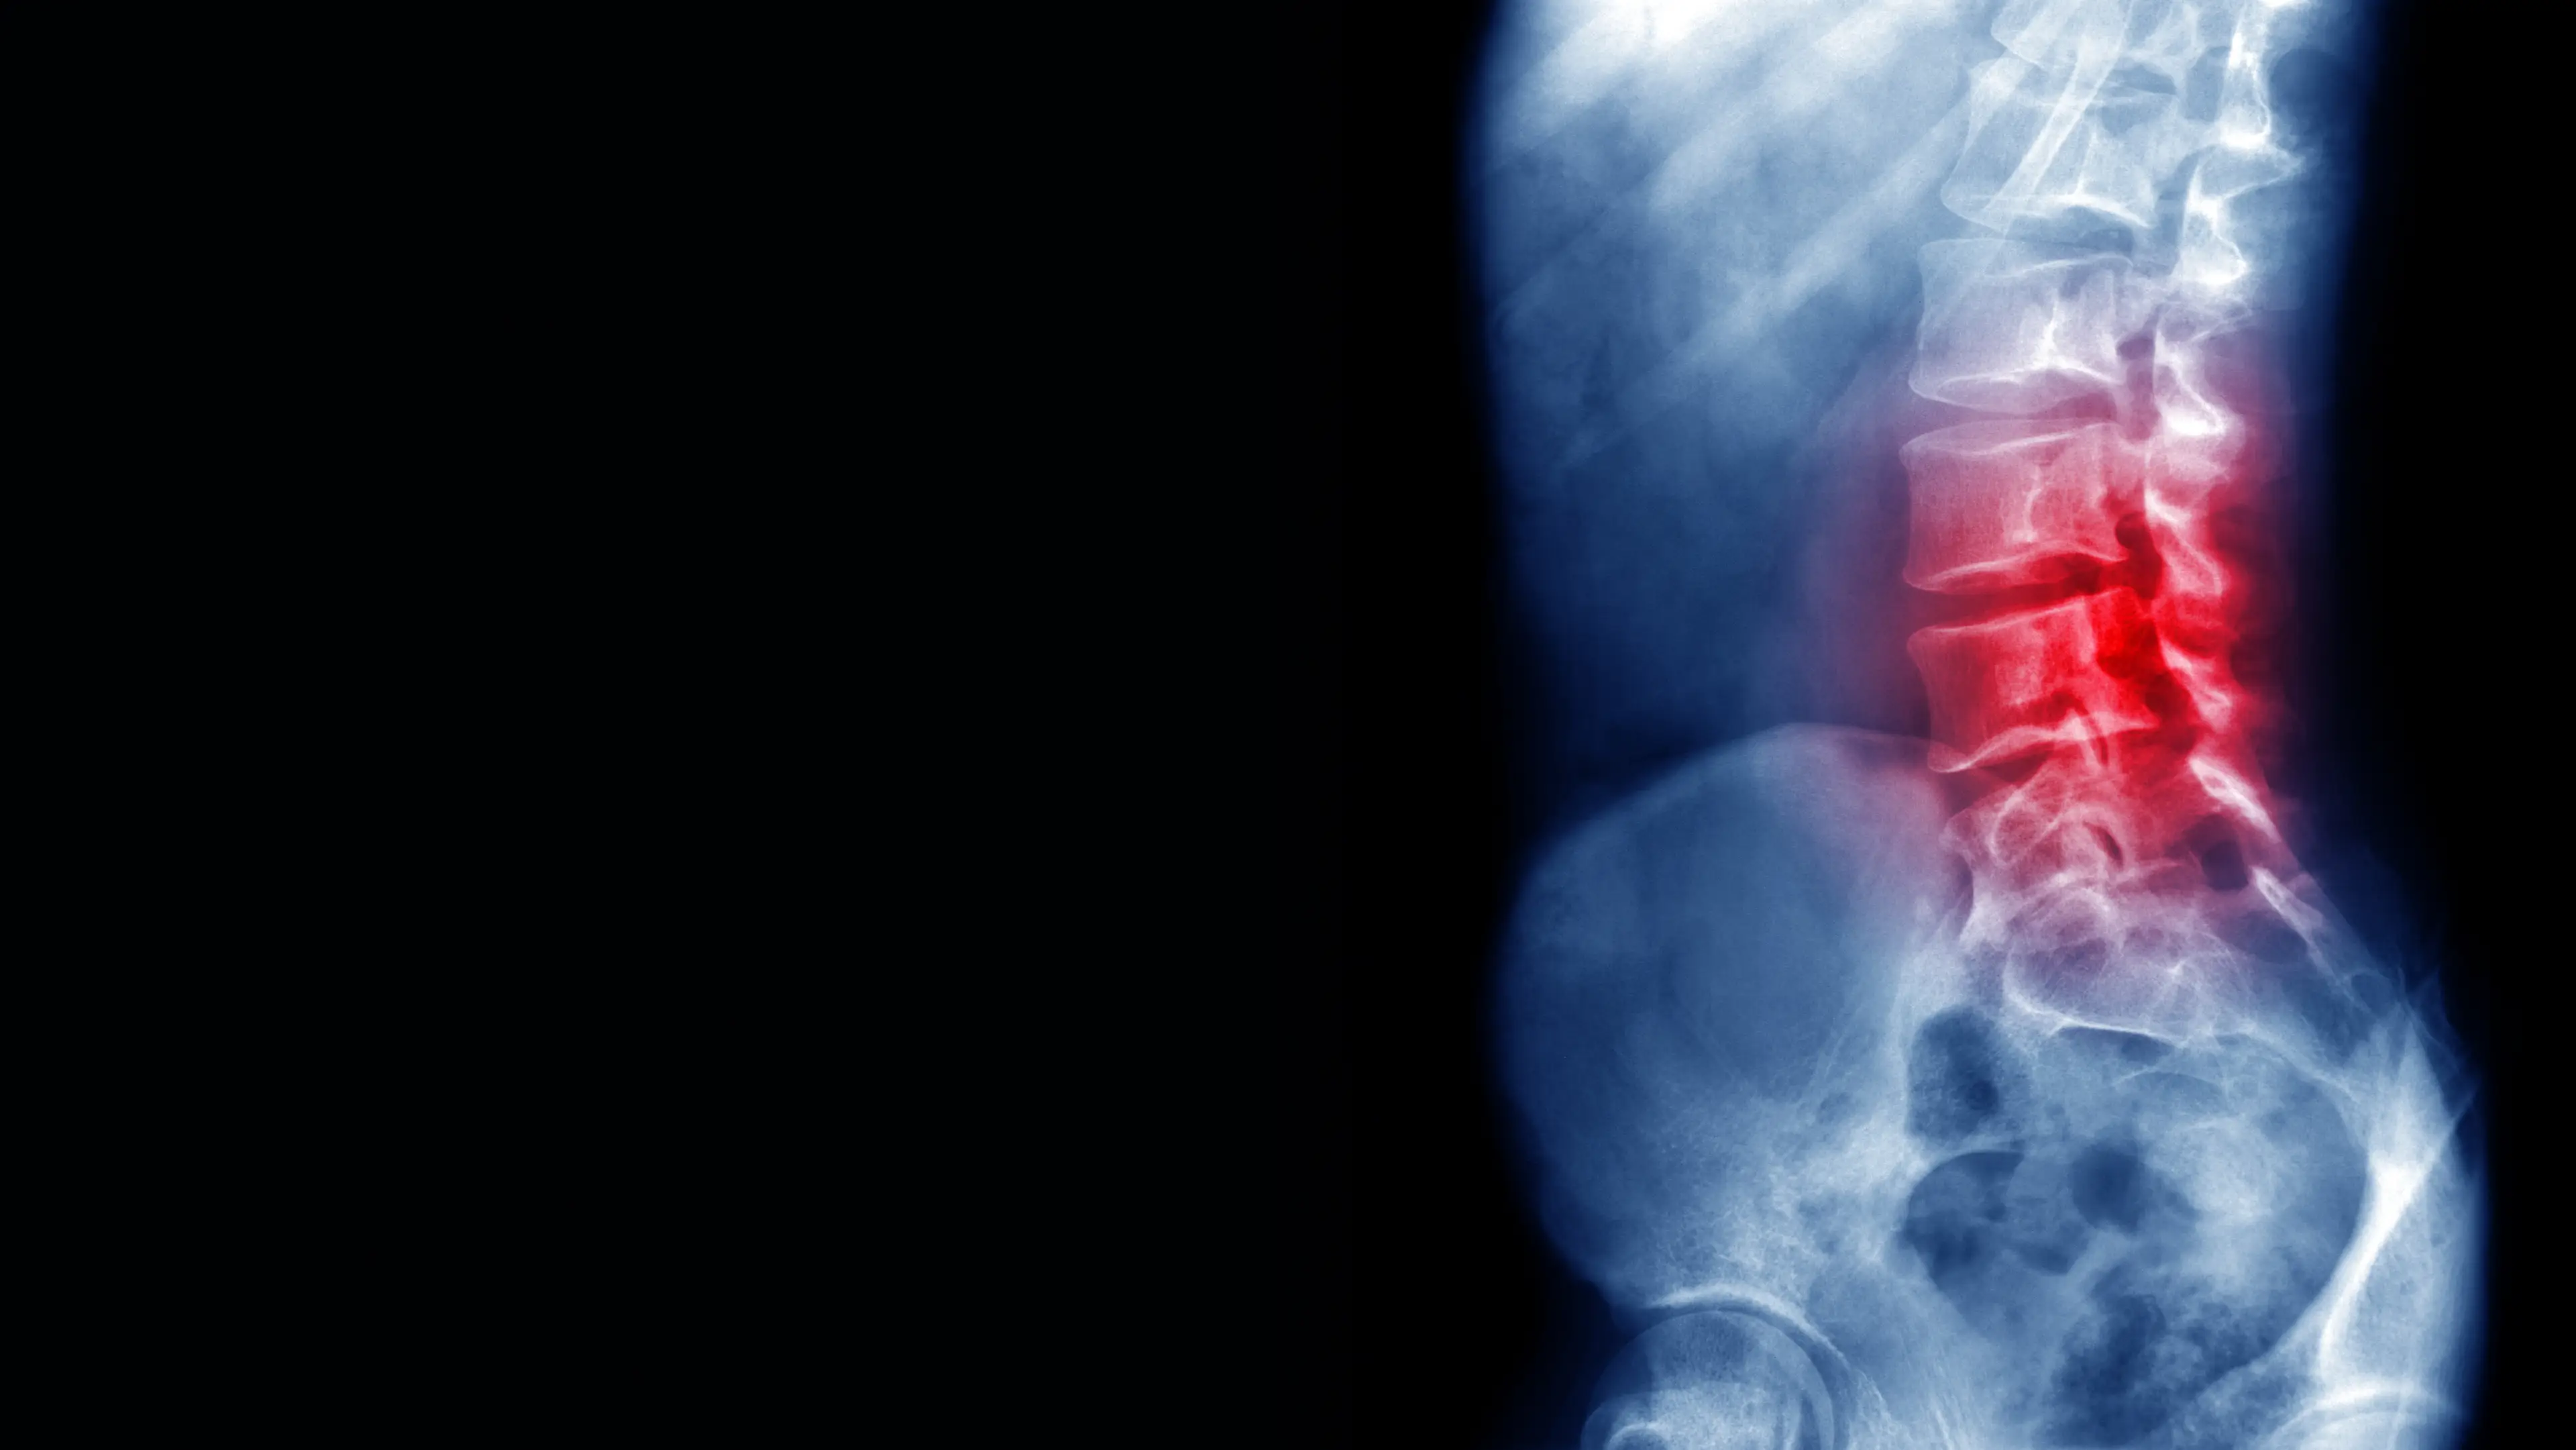

From sitting slouched over our phones to bad posture while working at a desk, it's easier than ever to trigger lower back pain earlier in life. But there are ways to alleviate it, according to medical experts.

More than 5.5 million people have high-impact chronic pain across the country, PHE revealed, with it found more prominently in people with back and neck pain. Across the world, back pain impacts 540 million people.